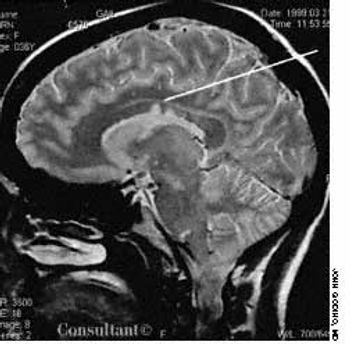

A 29-year-old woman complained of 6 months of tinnitus, hearing loss in the left ear, and leff-sided facial numbness. There was no history of trauma or recognized antecedent infection. Physical examination of the external and middle ears was unremarkable. Vestibular test results and tympanometry results were normal. An audiogram demonstrated nearly total sensorineural hearing loss in the left ear.